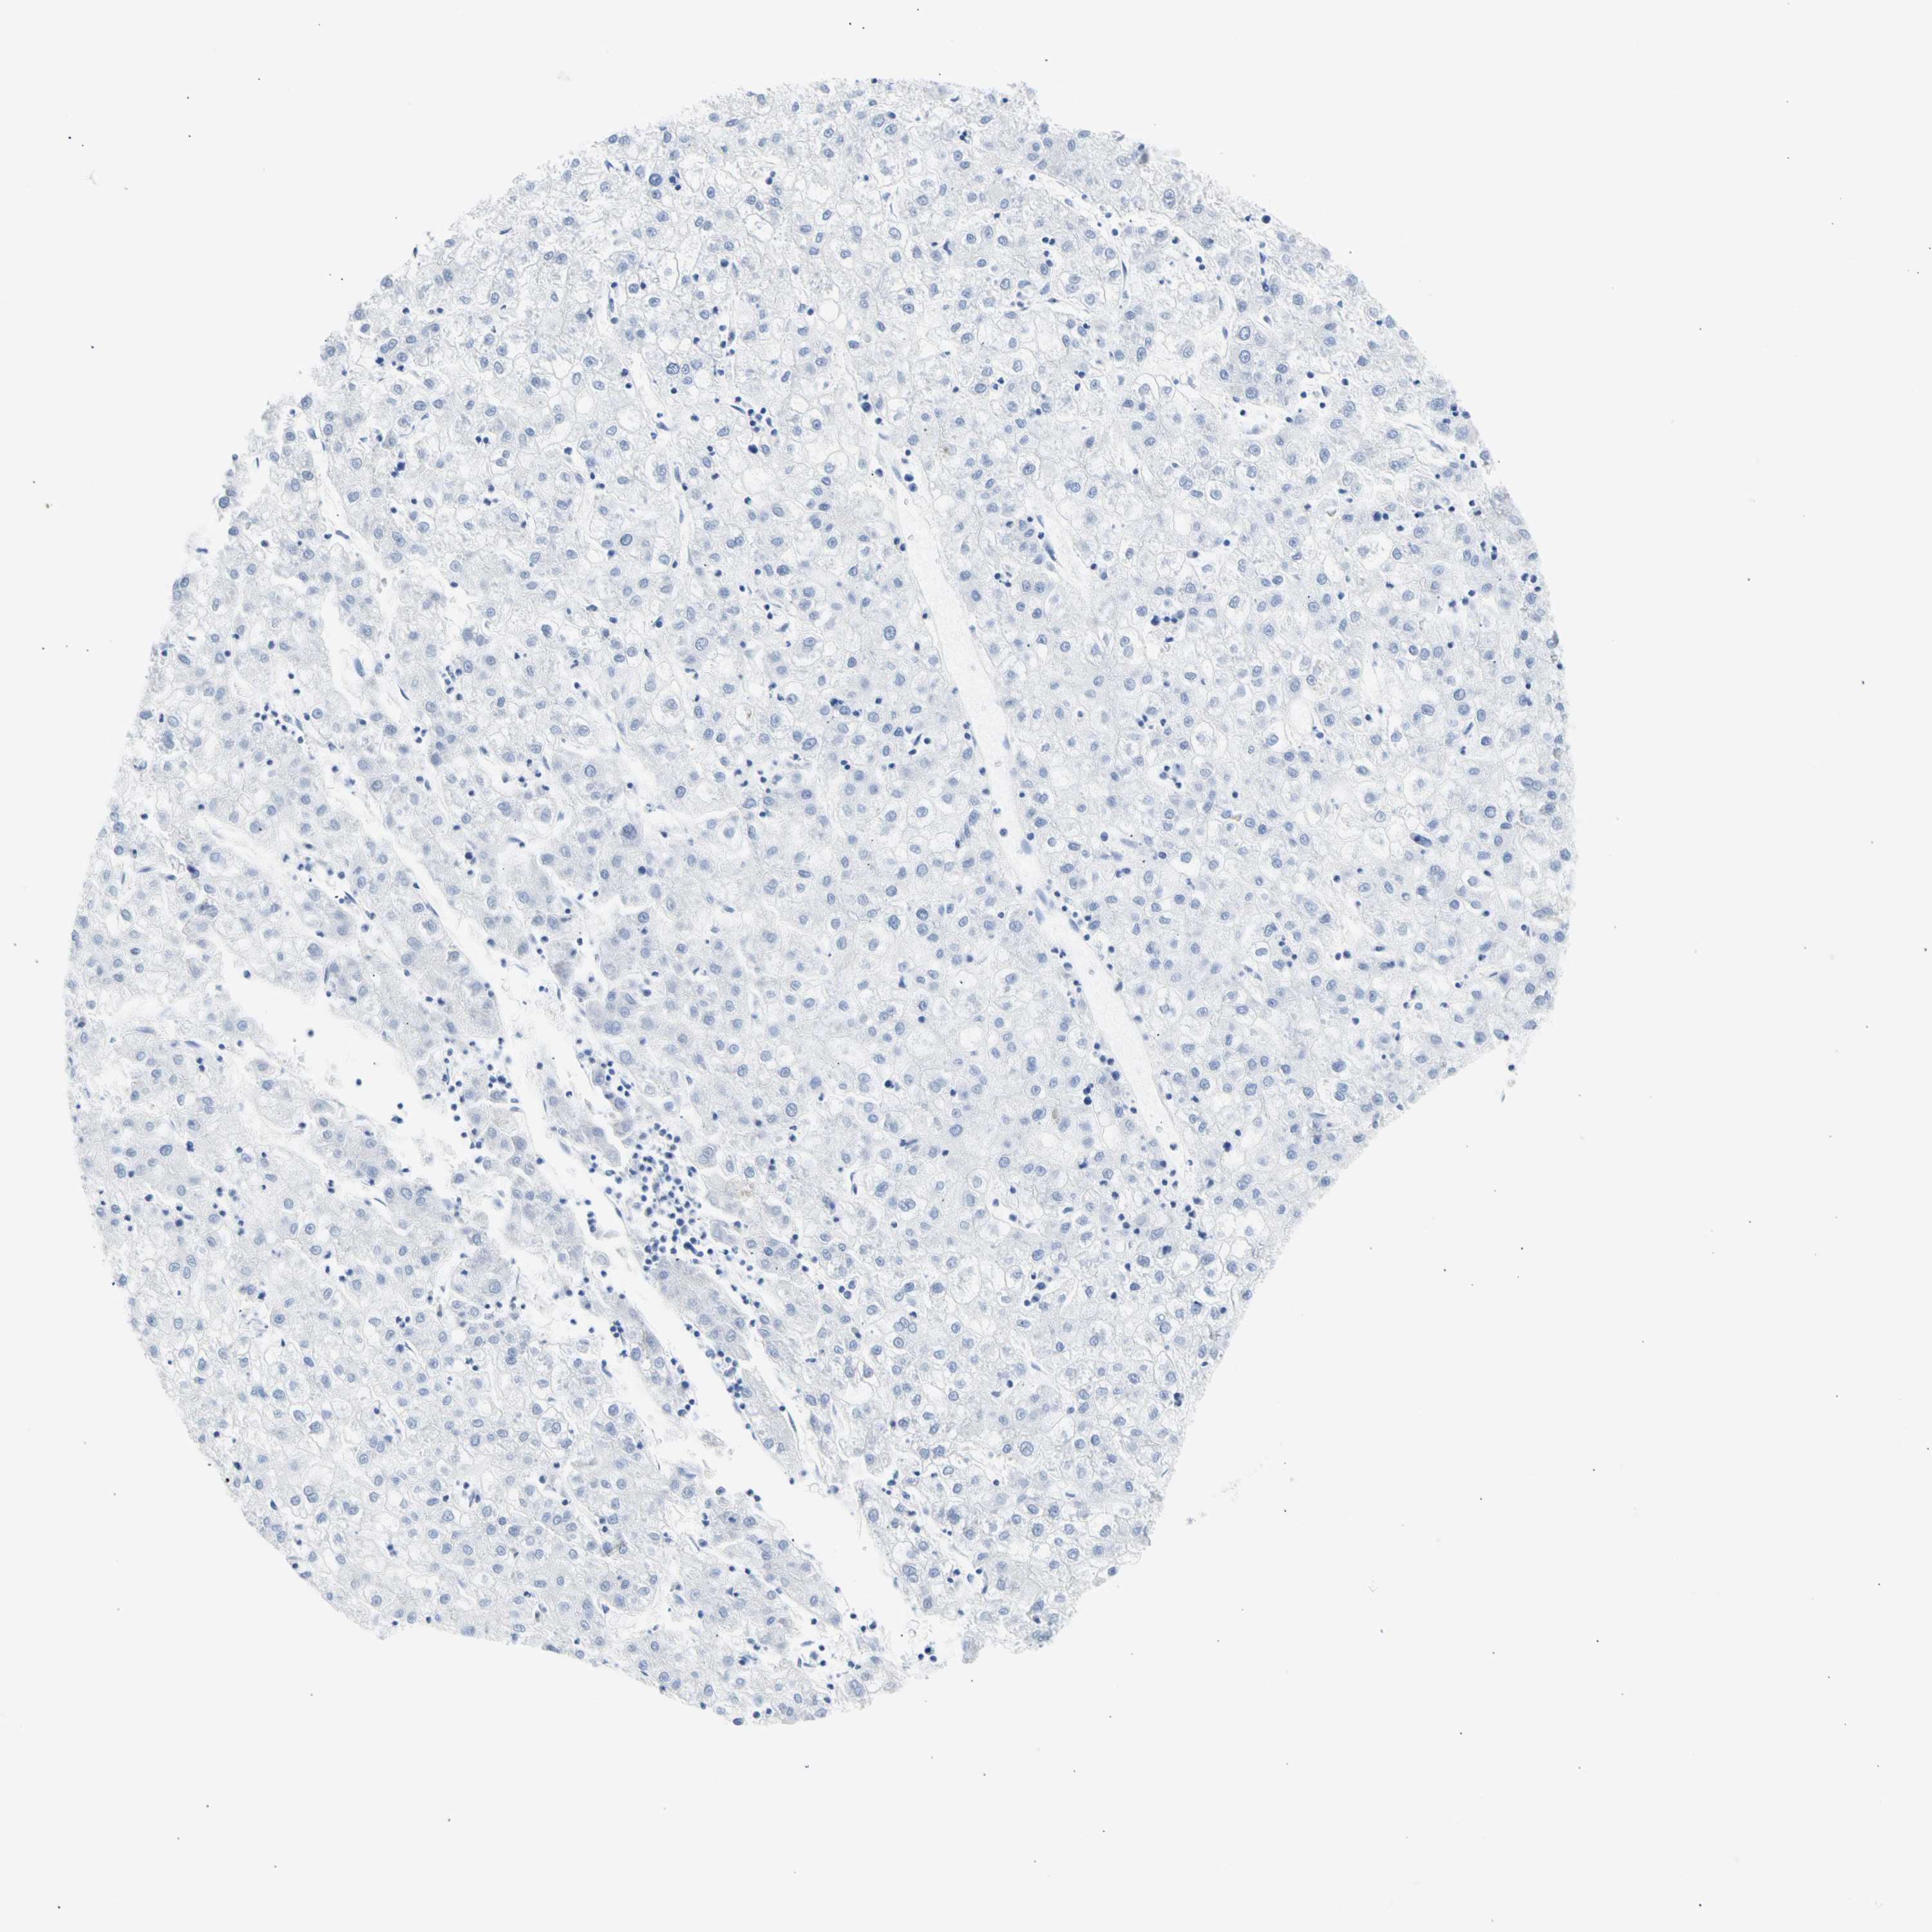

LIVER CANCER - Protein expressioni

A mouse-over function shows sample information and annotation data. Click on an image to view it in a full screen mode. Samples can be filtered based on level of antibody staining by selecting one or several of the following categories: high, medium, low and not detected. The assay and annotation is described here.

Note that samples used for immunohistochemistry by the Human Protein Atlas do not correspond to samples in the TCGA dataset.

Antibody stainingi

Antibody staining in the annotated cell types in the current human tissue is reported as not detected, low, medium, or high, based on conventional immunohistochemistry profiling in selected tissues. This score is based on the combination of the staining intensity and fraction of stained cells.

Each image is clickable and will lead to virtual microscopy that enables deeper exploration of all samples and also displays staining intensity scores, fraction scores and subcellular localization as well as patient and tissue information for each sample.

Antibody HPA008023

Antibody HPA052701

Staining

High

Medium

Low

Not detected

Intensity

Strong

Moderate

Weak

Negative

Quantity

>75%

75%-25%

<25%

None

Location

Nuclear

Cytoplasmic/membranous

Cytoplasmic/membranous,nuclear

Cholangiocarcinoma

Carcinoma, Hepatocellular, NOS